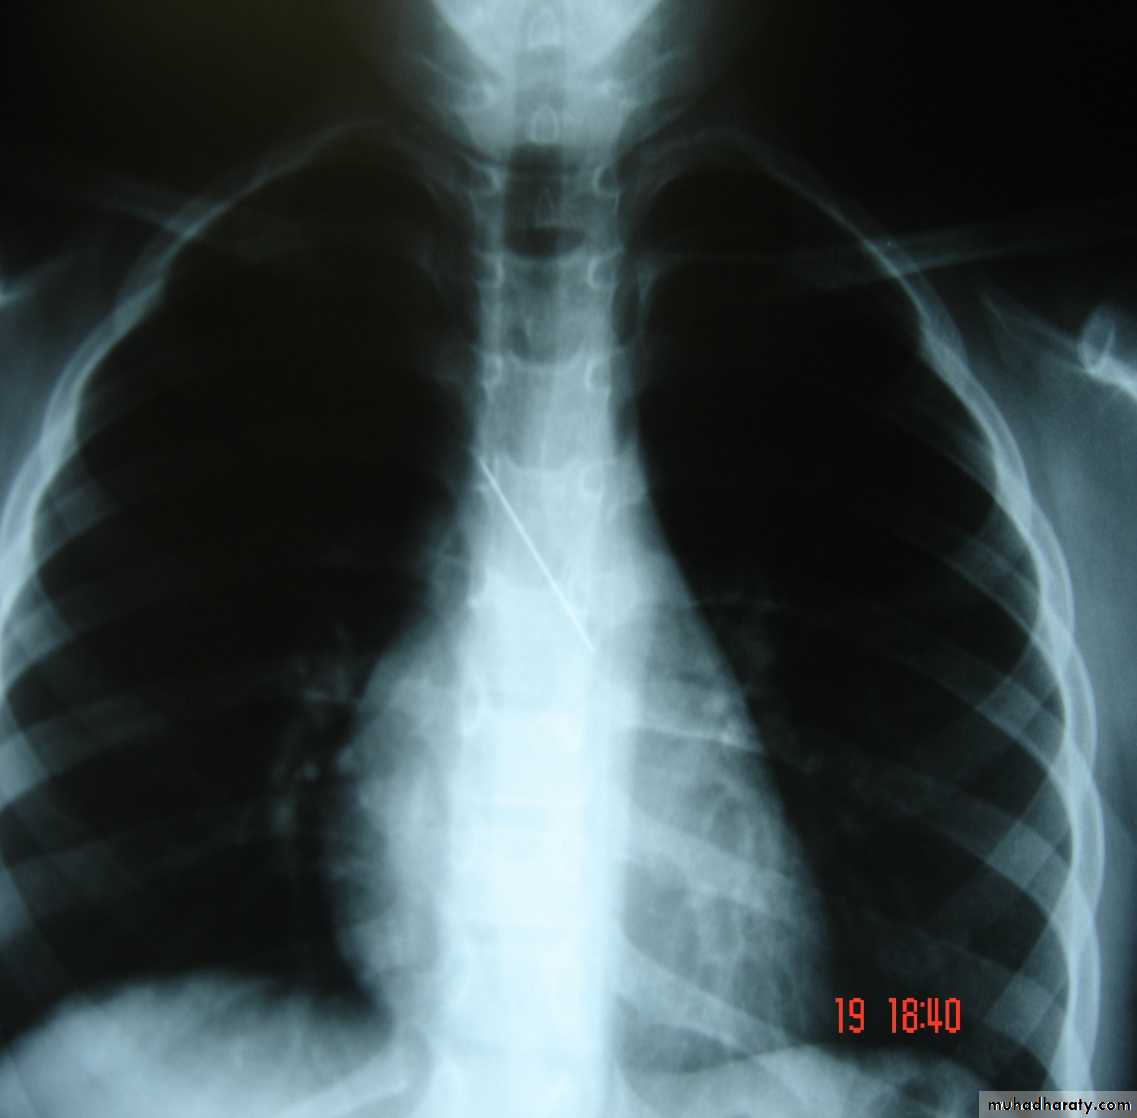

• Pneumothorax , bronchospasm , Bronchial perforation (Surgical emphysema & tension pneumothorax ) ,

• 3-Some may advise routine CXR after performing a biopsy to check for signs of pneumothorax .